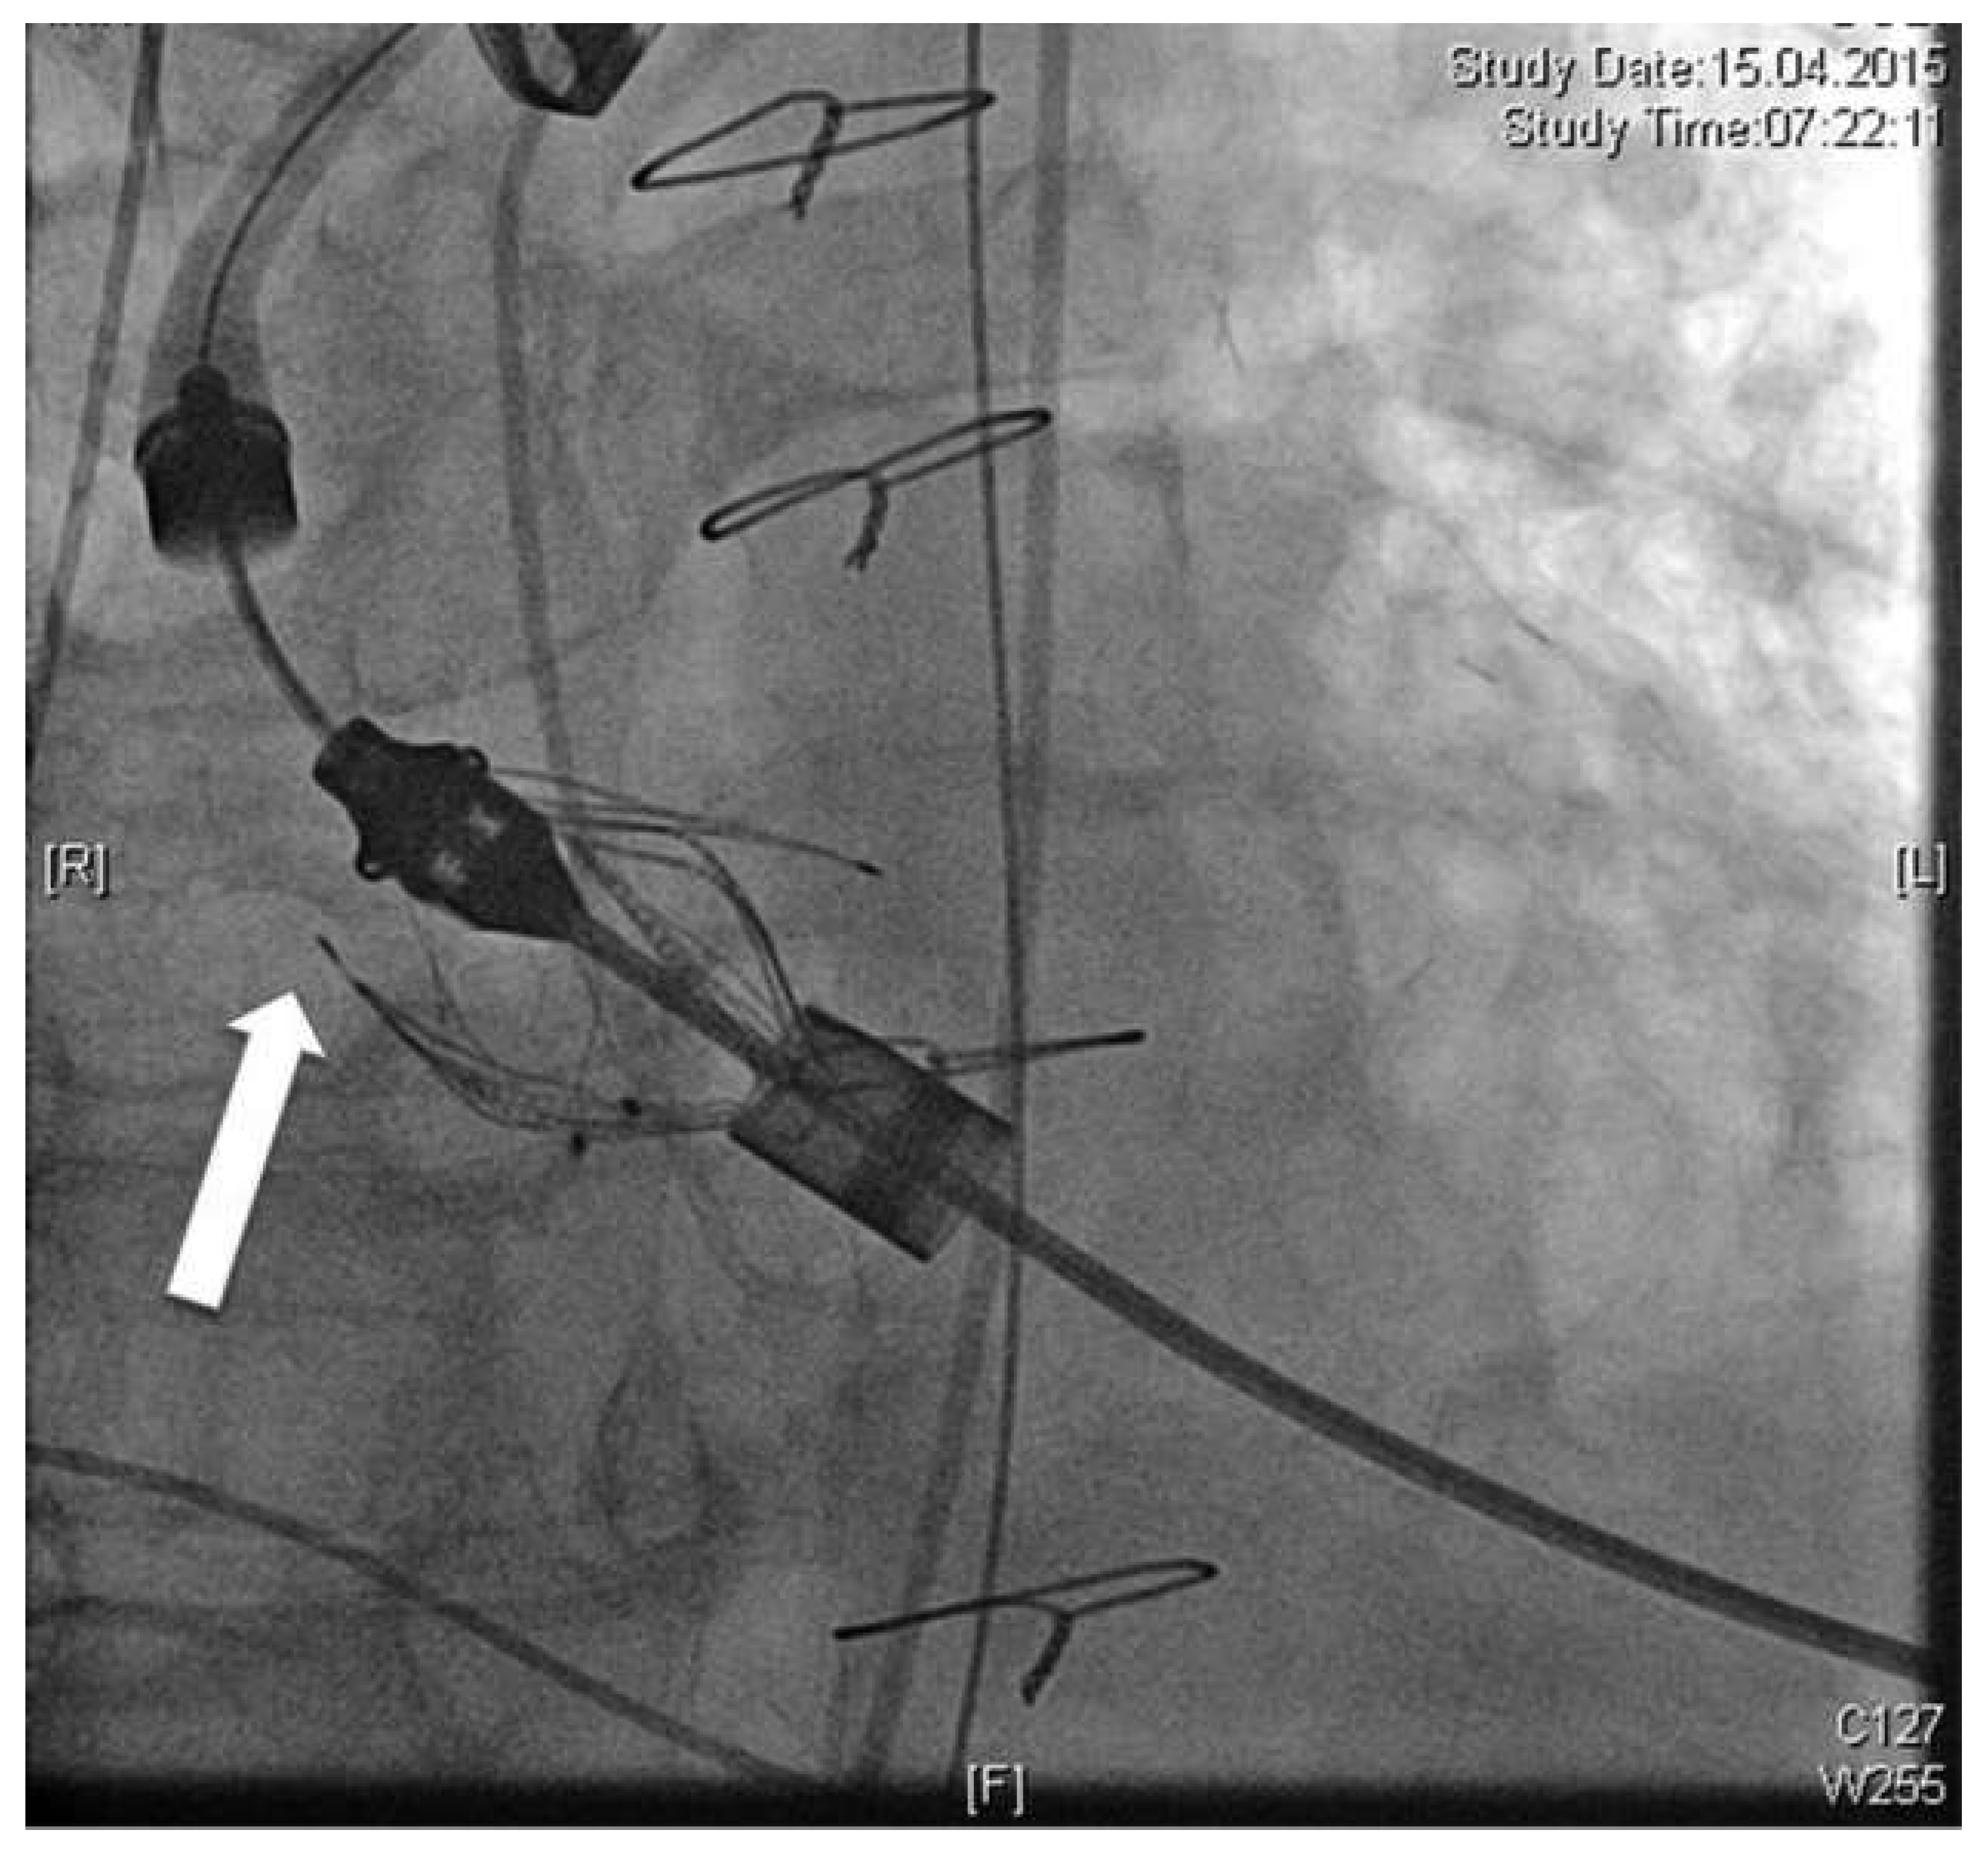

Under general anaesthesia the apex was accessed in the fifth intercostal space. Pericardial adhesions were detached and purse-string sutures applied. Under rapid pacing, straight valvuloplasty was performed and the JenaValveTM subsequently introduced. After release of the positioning feelers they were placed in the sinuses of the native valve. Because of imperfect positioning, the feelers of the JenaValveTM were repositioned. Simultaneously, one of the three eyelets of the crown inadvertently popped out of the catheter tip (Figure 1). Thus the valve became immobile and could no longer be replaced or removed. It had to be finally released at the level of the sinotubular junction. Severe paravalvular leakage could be determined angiographically and echocardiographically. Fortunately the patient was haemodynamically stable and no signs of myocardial ischaemia were detected. Because of the severe atherosclerosis of the native coronaries, as well as the sufficient myocardial perfusion via bypass grafts, conventional reoperation with sternotomy as bailout was rejected and implantation of a second TAVI prosthesis favoured instead. Therefore, a 26-mm Sapien S3 valve (Edwards, Irvine, USA) was chosen and uneventfully implanted transapically. The prosthesis was positioned directly beneath the JenaValveTM resulting in a valve-under-valve situation (Figure 2). Angiography and echocardiography revealed overall minimal paravalvular leakage at the level of the right coronary sinus with a total mean gradient of 8 mm Hg. After 145 minutes of total procedure time, the patient was extubated in the hybrid room with no inotropic support and without any neurological deficit. Maximum troponin T was 0.313 μg/l. After 24 hours of intensive care he was transferred to the normal ward and discharged from hospital on postoperative day 9. Predischarge ECG-triggered CT angiography showed both TAVI prostheses in situ, no signs of perforation and perfused bypass grafts. Predischarge transthoracic echocardiography confirmed the minimal paravalvular leakage and an acceptable gradient of mean 12 mm Hg. One year after discharge the patient was presenting well. His latest echocardiographic follow-up (April 2016) revealed a slightly reduced ejection fraction (50%), mild paravalvular leakage (grade 1) as well as a peak/mean pressure gradient of 16/8 mm Hg.

Figure 2. Post-implantation angiography showing both valves on top of each other: JenaValveTM (cross) as well as Edwards Sapien S3 (star).